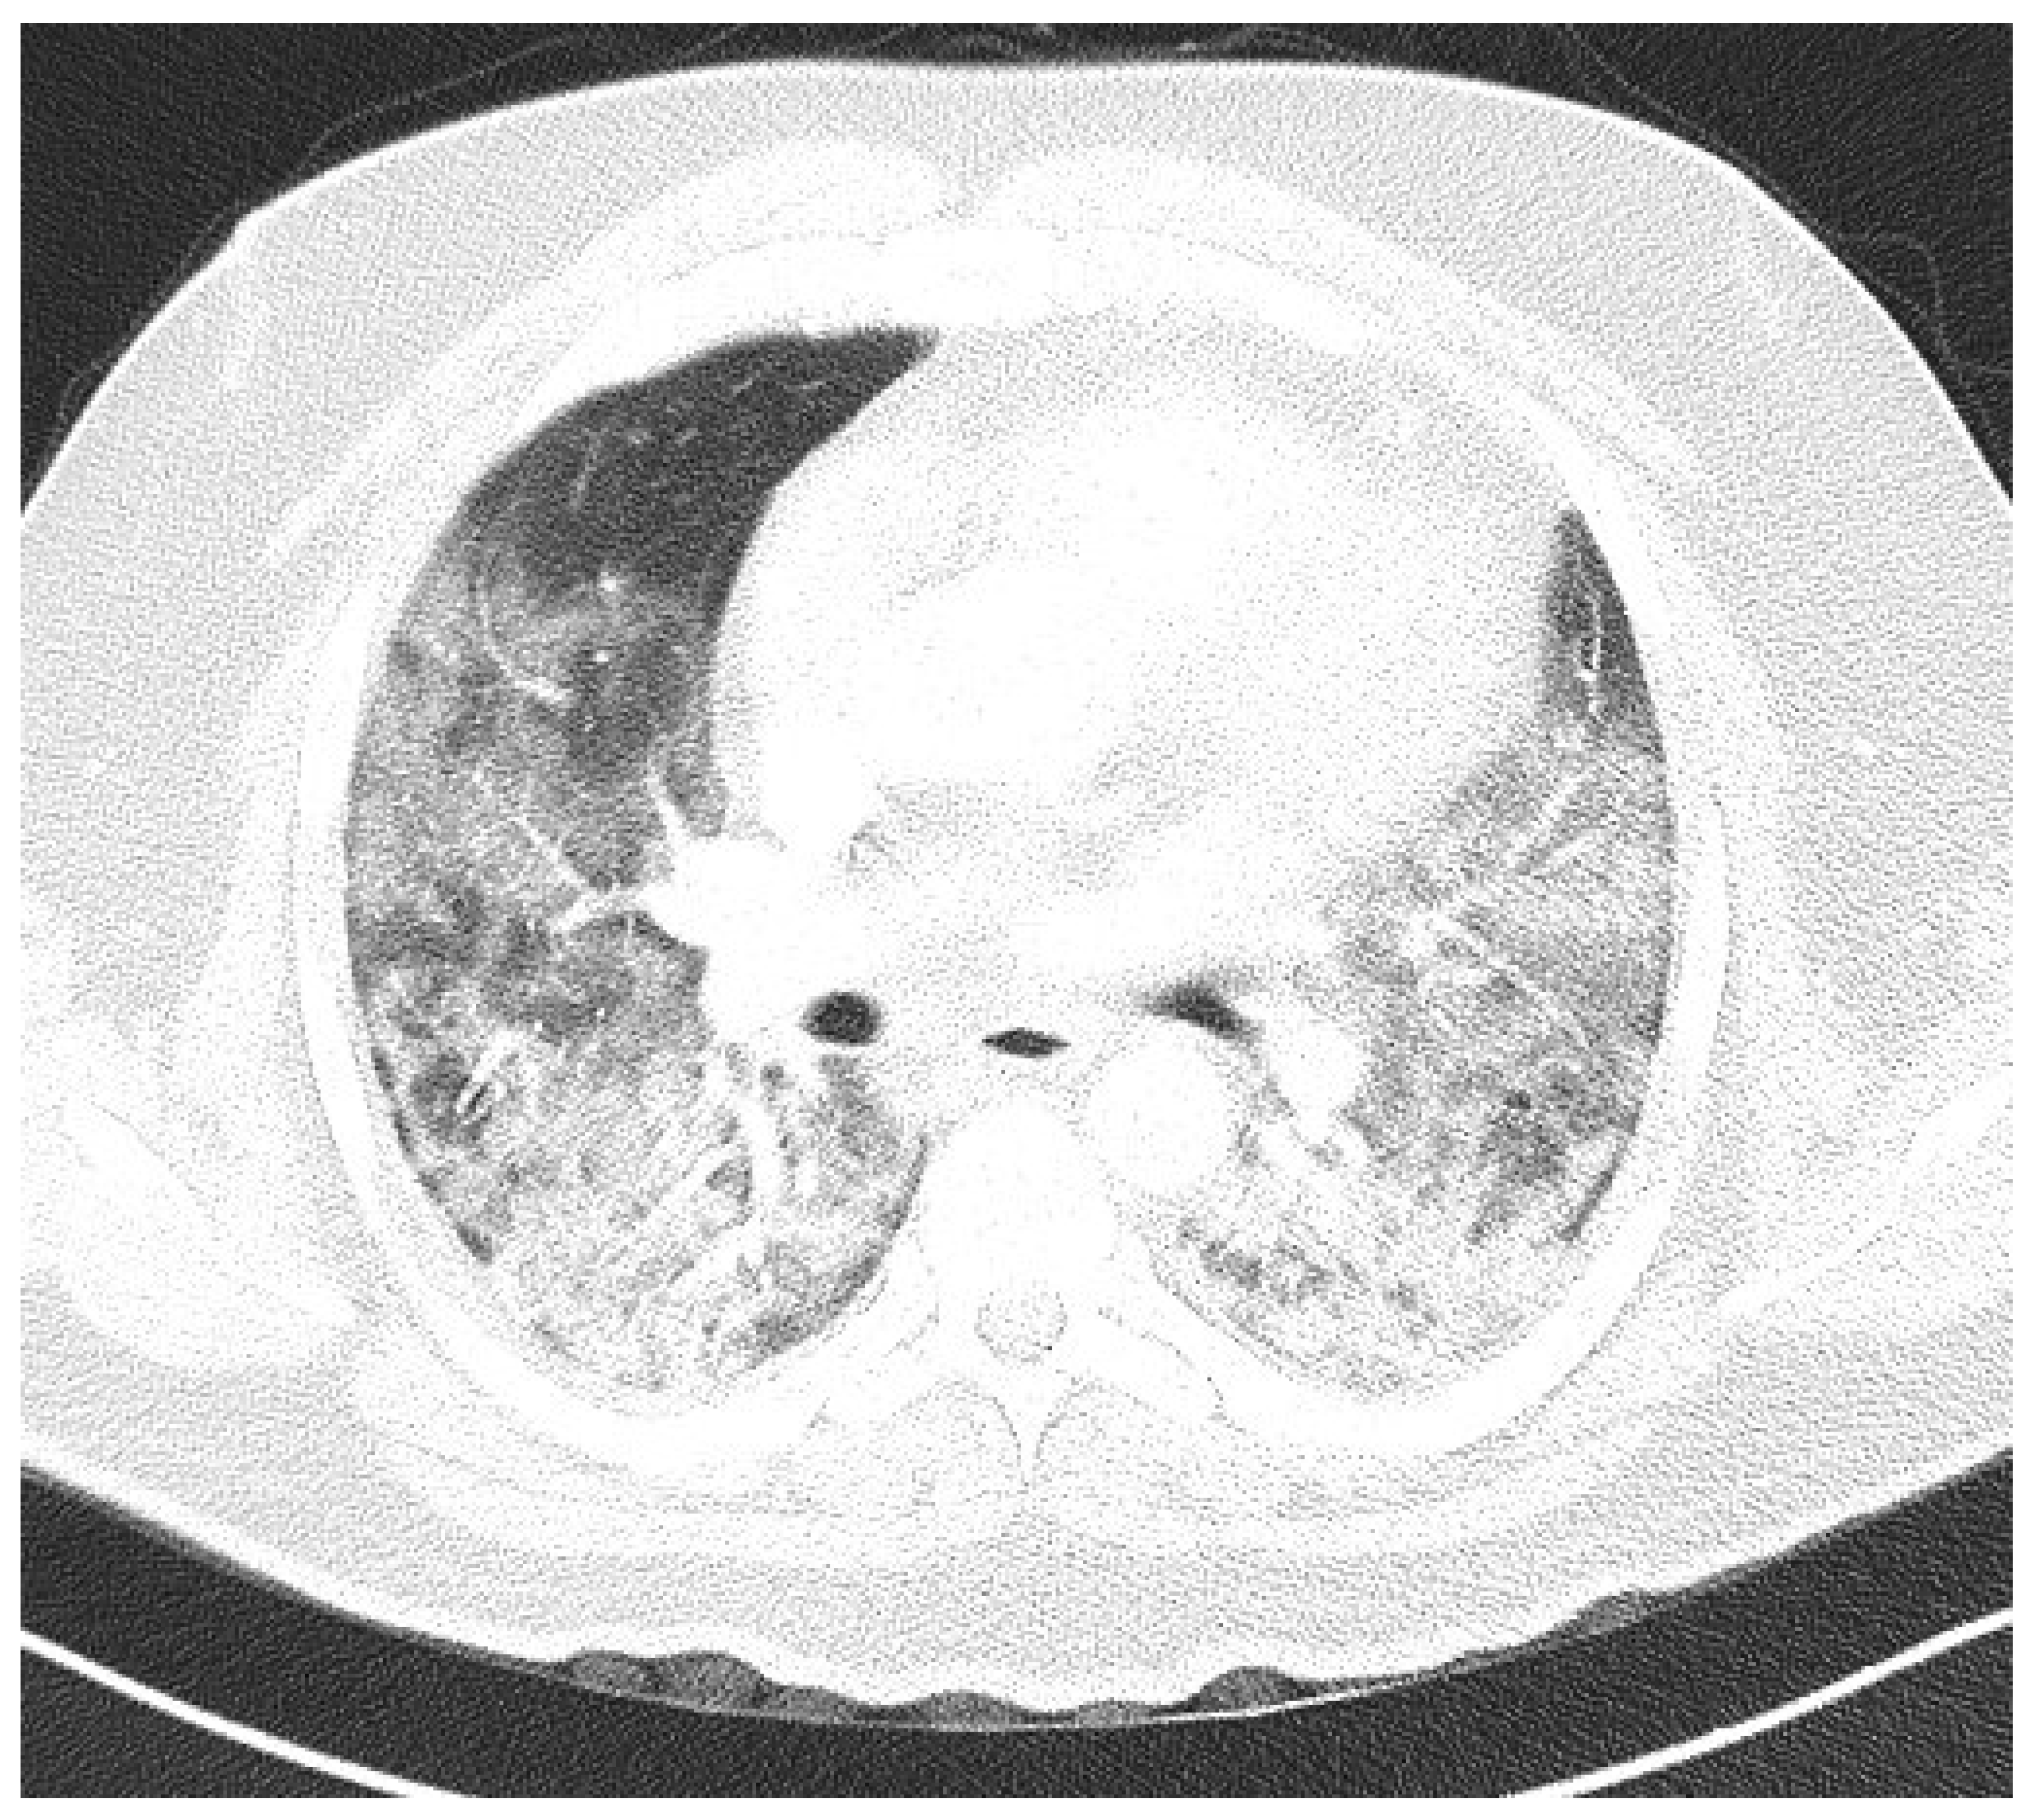

Laboratory findings were mostly normal; C-reactive protein was elevated in all patients with a mean value of 129.7 ± 80.74 mg/L. The arterial blood gas analysis showed hypoxemic respiratory failure. Chest X-rays in all patients showed bilateral inhomogeneous infiltrates (Figure 1 and Figure 2). In three patients, CTPA was performed, which ruled out pulmonary thromboembolism, but ground-glass opacifications with consolidation of the lung parenchyma were described in all of them (Figure 3 and Figure 4) [15].

Figure 4. CTPA upon admittance: patient 4. Bilateral ground glass opacifications (severity score: 19–25) typical for COVID-19 pneumonia.